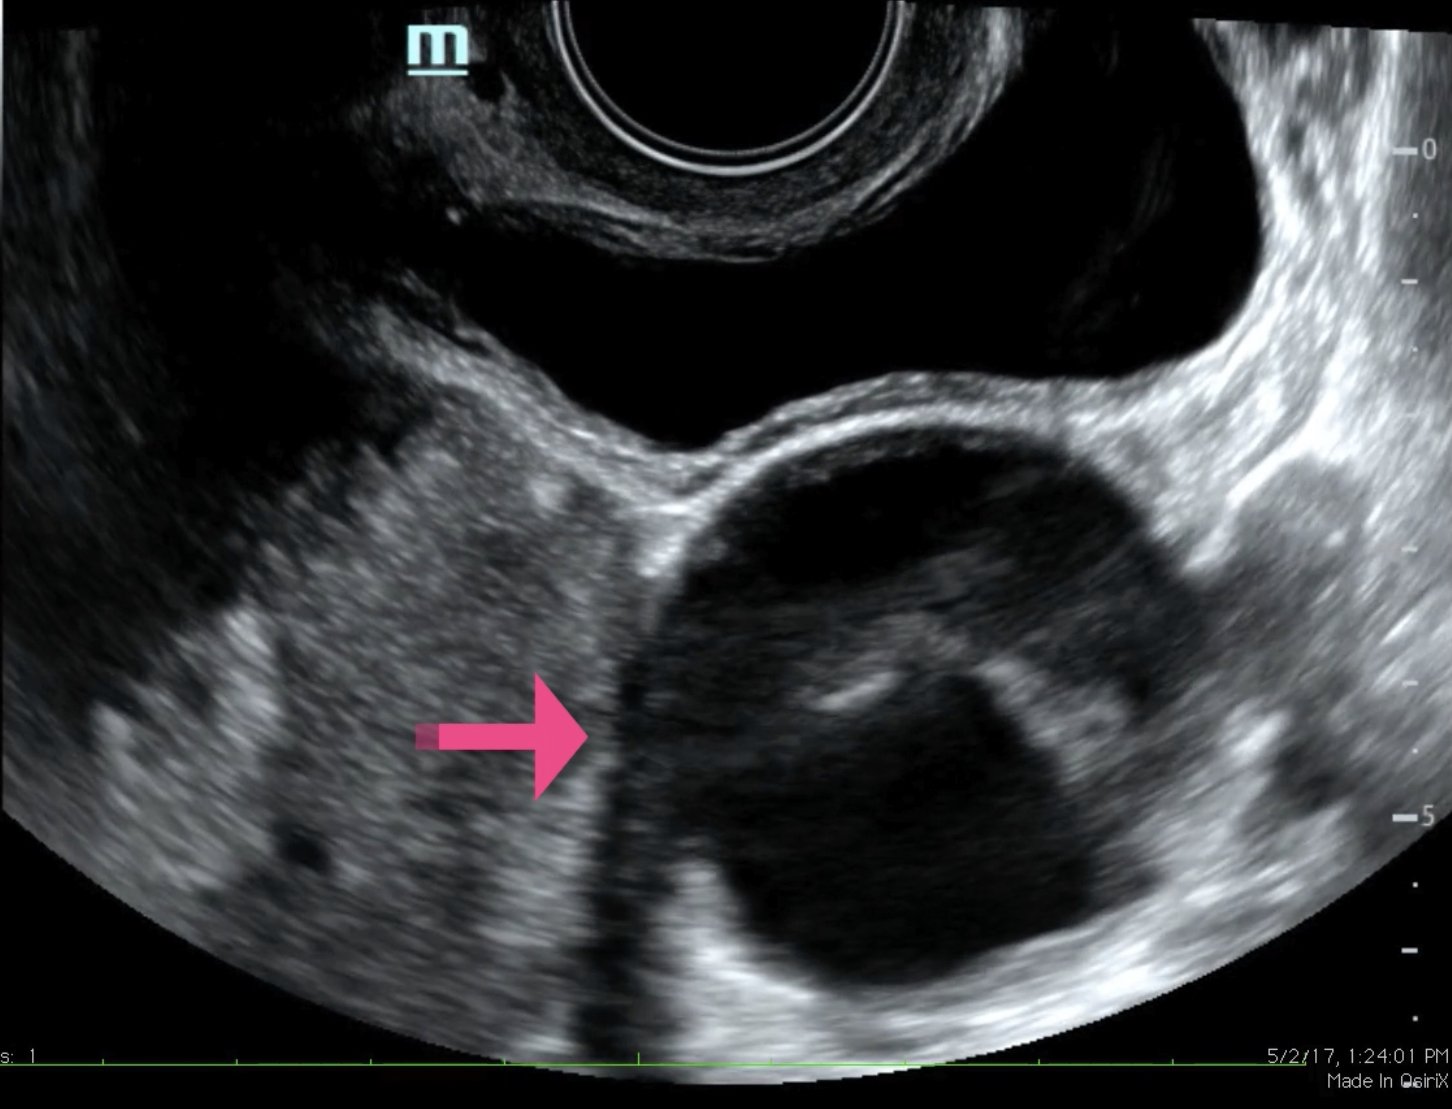

The ultrasound video clip demonstrates a transverse view of the pelvis using the endocavitary probe. The bladder can be seen on the anterior portion of the scan (yellow arrow), while the uterus with an intrauterine pregnancy is visible posteriorly (blue arrow). The thickened appearance of the uterine wall is also indicative of pregnancy. A large, anechoic cystic structure measuring approximately 5 cm is seen in the vicinity of the patient’s left adnexa (pink arrow), which raises concerns for ovarian torsion.1

Based on the clinical presentation and the bedside ultrasound, obstetrician-gynecologist (OB/gyn) was emergently consulted and the patient was transferred to the operating room (OR) where she was found to have a paratubal cyst in the left fallopian tube with associated isolated tubal torsion. After manually de-torsing the tube, which was initially dilated and dusky, blood flow was restored and the color returned to normal. A cystectomy was performed without complications. The patient was discharged later that day after the follow-up ultrasound showed reassuring fetal heart tones and good blood flow to the left ovary.

When using bedside ultrasound, the most reliable indicator of ovarian torsion is an enlarged ovary, greater than 4 cm in size.3In addition to looking for an enlarged ovary, additional sonographic findings that can be indicative of torsion include a solid, cystic, or complex mass, with or without fluid, or cystic hemorrhage.4 Ovarian cysts are risk factors due to their capacity to serve as pivot points for ovaries to twist around.1,4 When performing the ultrasound, it is possible to see little or no intra-ovarian venous flow or absent arterial flow, but because there is dual blood supply to the ovaries from the ovarian and uterine arteries, normal vascularity does not exclude torsion.